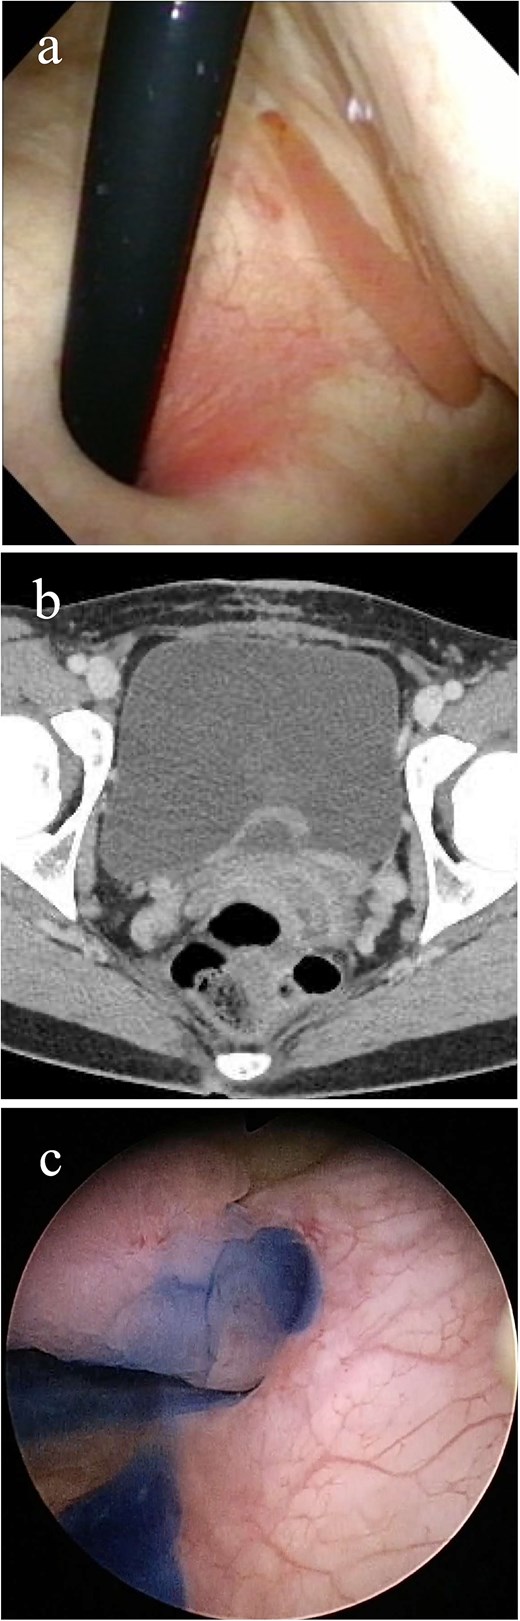

A 32-year-old Japanese woman presented to our hospital with painless intermittent gross hematuria that had persisted for 5 months. She had no history of urolithiasis or urinary tract infections. Her blood test results were within normal limits. Although urine analysis revealed microscopic hematuria, urine culture, and cytology tests were negative. Cystoscopy performed in the outpatient clinic revealed a smooth-surfaced snake-like tumor protruding from the left ureteral orifice into the bladder lumen, moving like snake’s crawling with respiratory movements (Fig. 1a). Contrast-enhanced computed tomography (CT) revealed a 3-cm-long soft tissue shadow around the left ureteral orifice (Fig. 1b). Urolithiasis or hydronephrosis was not observed.

Imaging study findings. (a) Cystoscopy finding. Cystoscopy revealed that a tumor protruded from the left ureteral orifice into the bladder lumen, showing serpentine locomotion with respiratory movements. (b) Contrast enhanced computed tomography finding. Soft tissue shadow was detected around the left ureteral orifice, revealing a long thin tumor. (c) Indigo carmine was excreted through the left orifice that is occupied by the tumor.

The patient underwent detailed endoscopy in the operating room (Video 1). The indigo carmine test revealed patency in the ureteral orifice occupied by the tumor (Fig. 1c). A ureteroscope was inserted along the tumor into the left ureter. The lower ureter was occupied nearly completely by the tumor, but the ureteroscope could pass through the small gap between the tumor and the ureteral wall. As the scope reached the mid-ureter, the root of the tumor eventually became thinner, and a single narrow base of the tumor was identified. FEP was diagnosed based on the characteristic surface findings and root shape of the tumor. Because this polyp could be safely removed ureteroscopically, ureteroscopic resection was performed using a Holmium: YAG Laser (0.3 J, 10 Hz). Electrocautery was applied to the base of the polyp, and the coagulation area was kept as small as possible. Finally, the polyp was resected and extracted entirely from the ureter and into the bladder lumen using forceps. A double-J stent was inserted, and the ureteroscopic procedure was completed. The stent was removed a month after the surgery. Her gross hematuria stopped, and she reported no complications. Histopathological examination revealed a 9.5 cm tumor and a polyp with edematous stroma, which was confirmed to be ureteral FEP (Fig. 2a and b).